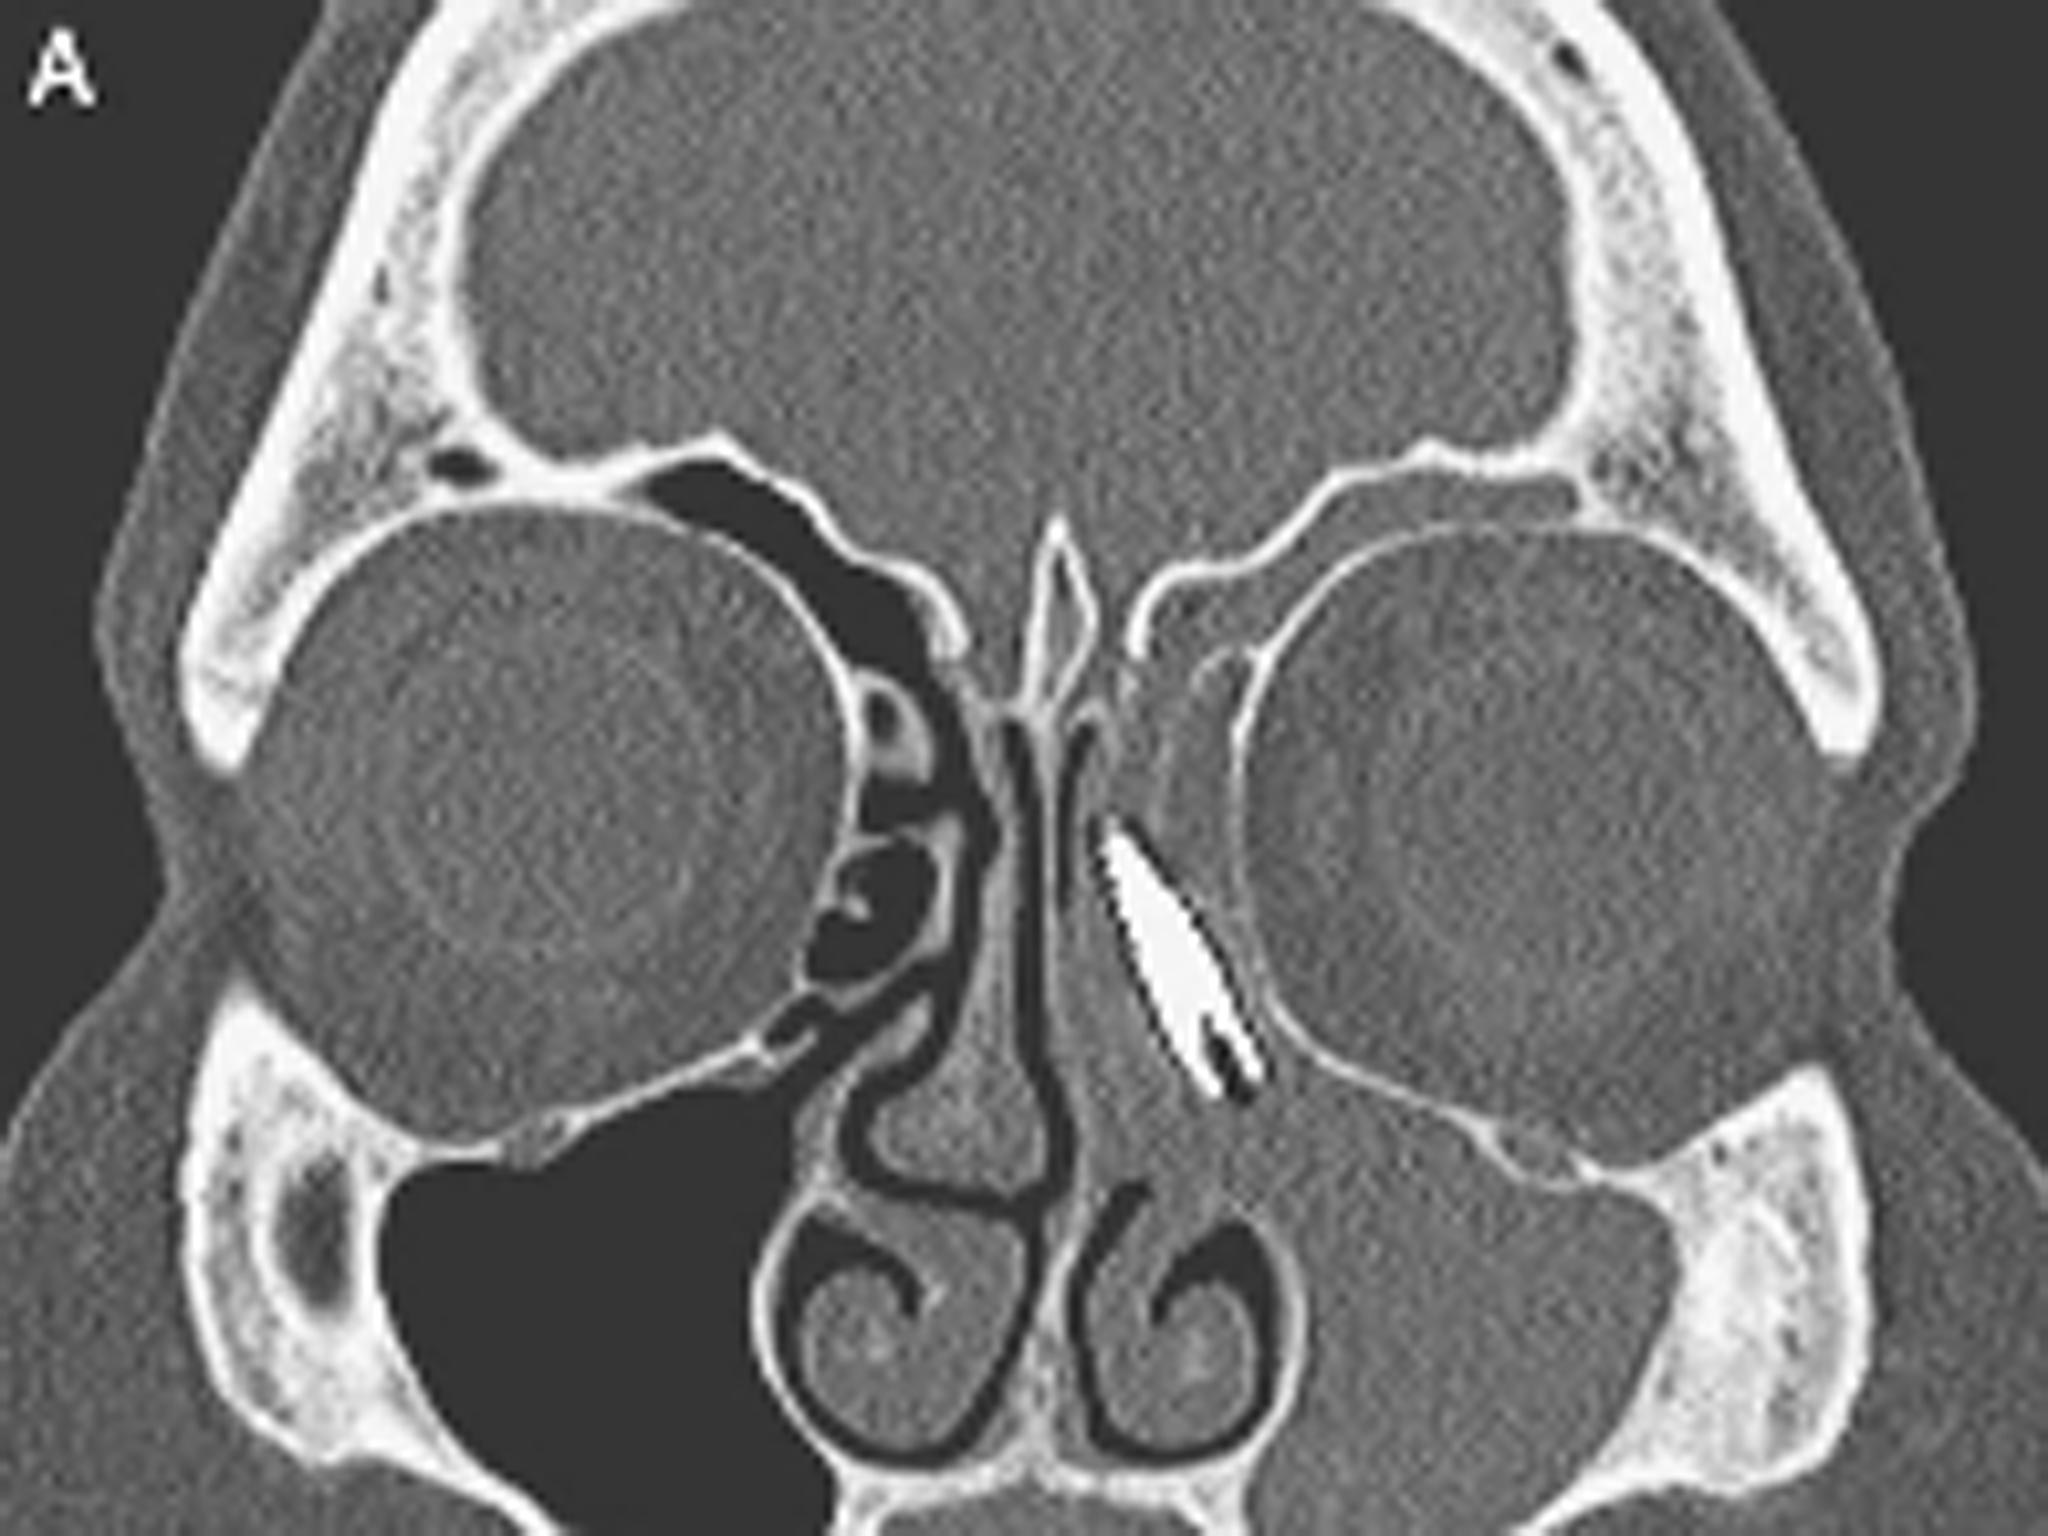

A metal screw was found next to her left eye which had migrated up from a dental implant

A CT scan revealed the screw had travelled into her nasal cavity and settled next to her left eye.